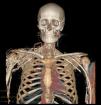

En la exploración física destacaba edema facial, dilatación de las venas del cuello e incremento del número de venas colaterales en la parte anterior del tórax, hombro y brazo derecho. En la radiografía de tórax se observó ensanchamiento del mediastino y derrame pleural subpulmonar bilateral. La tomografía computarizada (TC) de tórax mostró un mediastino ensanchado con trabeculación de la grasa y que ocasionaba un efecto masa que afectaba a la vena cava superior (fig. 1). La reconstrucción angiográfica en 3D mostró la extensa red de circulación colateral por obstrucción de la vena cava superior que se extendía hacia la pared torácica, los miembros superiores y el abdomen (fig. 2). No se evidenciaron trombos en la vena cava. Ante estos hallazgos, se diagnosticó como SVCS. Se realizó una flebografía para valorar la afectación vascular y colocar un stent endovascular con el objetivo de repermeabilizar la circulación venosa. Sin embargo, este tratamiento fue infructuoso debido a la existencia de una obstrucción total de las venas subclavias que dificultaba el acceso a la vena cava. Dada la obstrucción de la vena cava superior por un proceso infiltrativo mediastínico, se realizó mediastinotomía para filiar la causa responsable de dicho proceso. La biopsia mostró un tejido adiposo con escasa celularidad sin que se identificaran granulomas, calcificaciones ni células malignas. La prueba de la tuberculina no mostró induración, y el cultivo para micobacterias y hongos del broncoaspirado y del material de la biopsia fue negativo El paciente fue diagnosticado de SVCS por fibrosis mediastínica de origen idiopático.